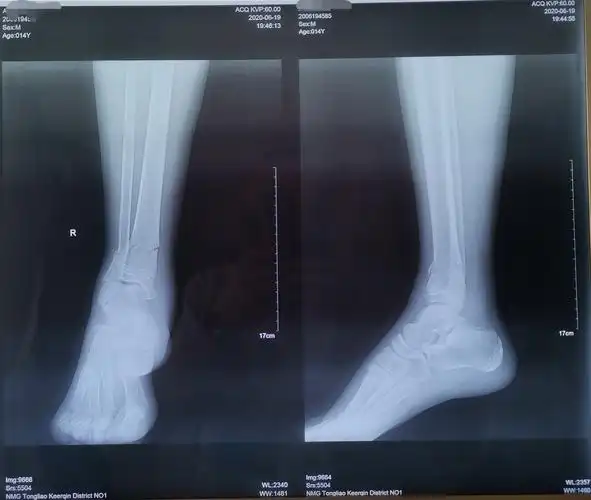

14岁胫腓骨远端骨折闭合复位外固定架固定手术一例

患者受伤后的dr正侧位x线照片:可以看出患者小腿胫腓骨双折,胫骨断段